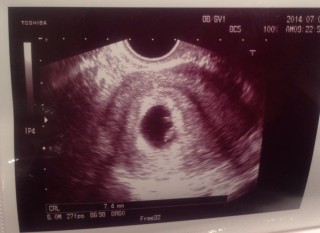

6w5d8.9mmでした!順調とのことで母子手帳もgetしてきました!